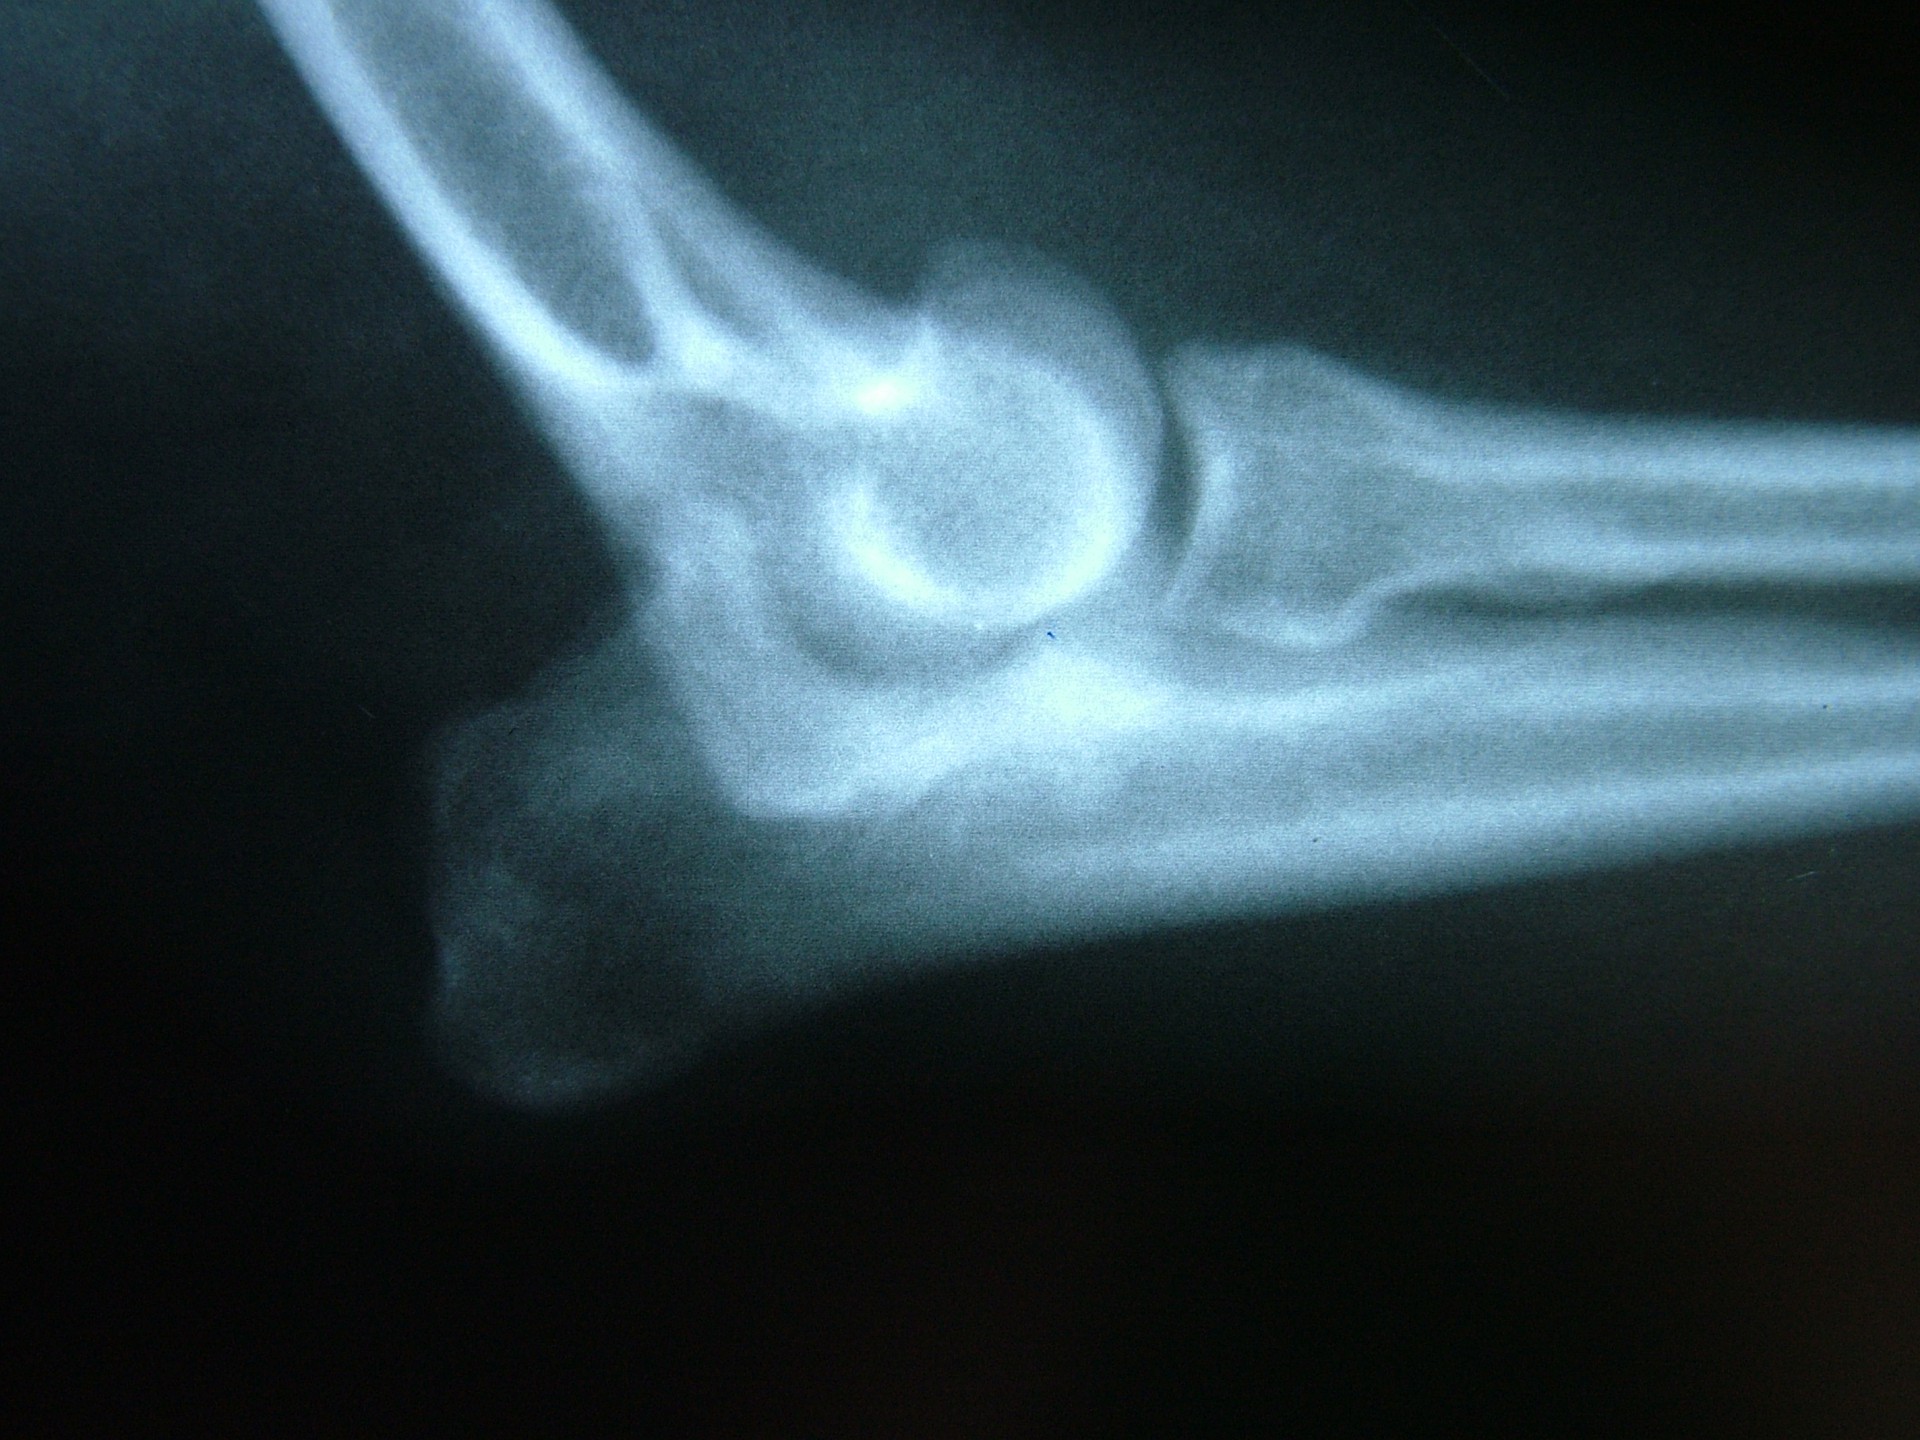

A könyökcsont növekedési zónájának záródása (short ulna)

A könyökcsont alsó epiphysisének lezáródása (short ulna) az alkar kifelé történő görbülését eredményezi (valgus állás). A klinikai tünetek (végtagdeformitás) mindig fokozatosan, lassan alakulnak ki, sok esetben a növekedési zóna lezáródásához vezető trauma nem igazolható. Az állat a lábát az elülső lábtőízület alatti területen kifelé fordítva tartja.A fizikális vizsgálat során fájdalom nem tapasztalható és az altatásban történő vizsgálat során a végtag deformitása nem szüntethető meg. A kiegészítő RTG vizsgálattal a könyökcsont alsó növekedési zónájának záródása egyértelműen igazolható. Ezek alapján a betegség az elülső lábtőízület lazaságától (carpal laxity) egyértelműen elkülöníthető. Mivel a végtagállási hiba már kölyök korban megjelenik fontos annak elkülönítése is, hogy örökletes úton (X-láb) vagy a növekedési zóna lezáródása következtében alakult ki a valgus állás.